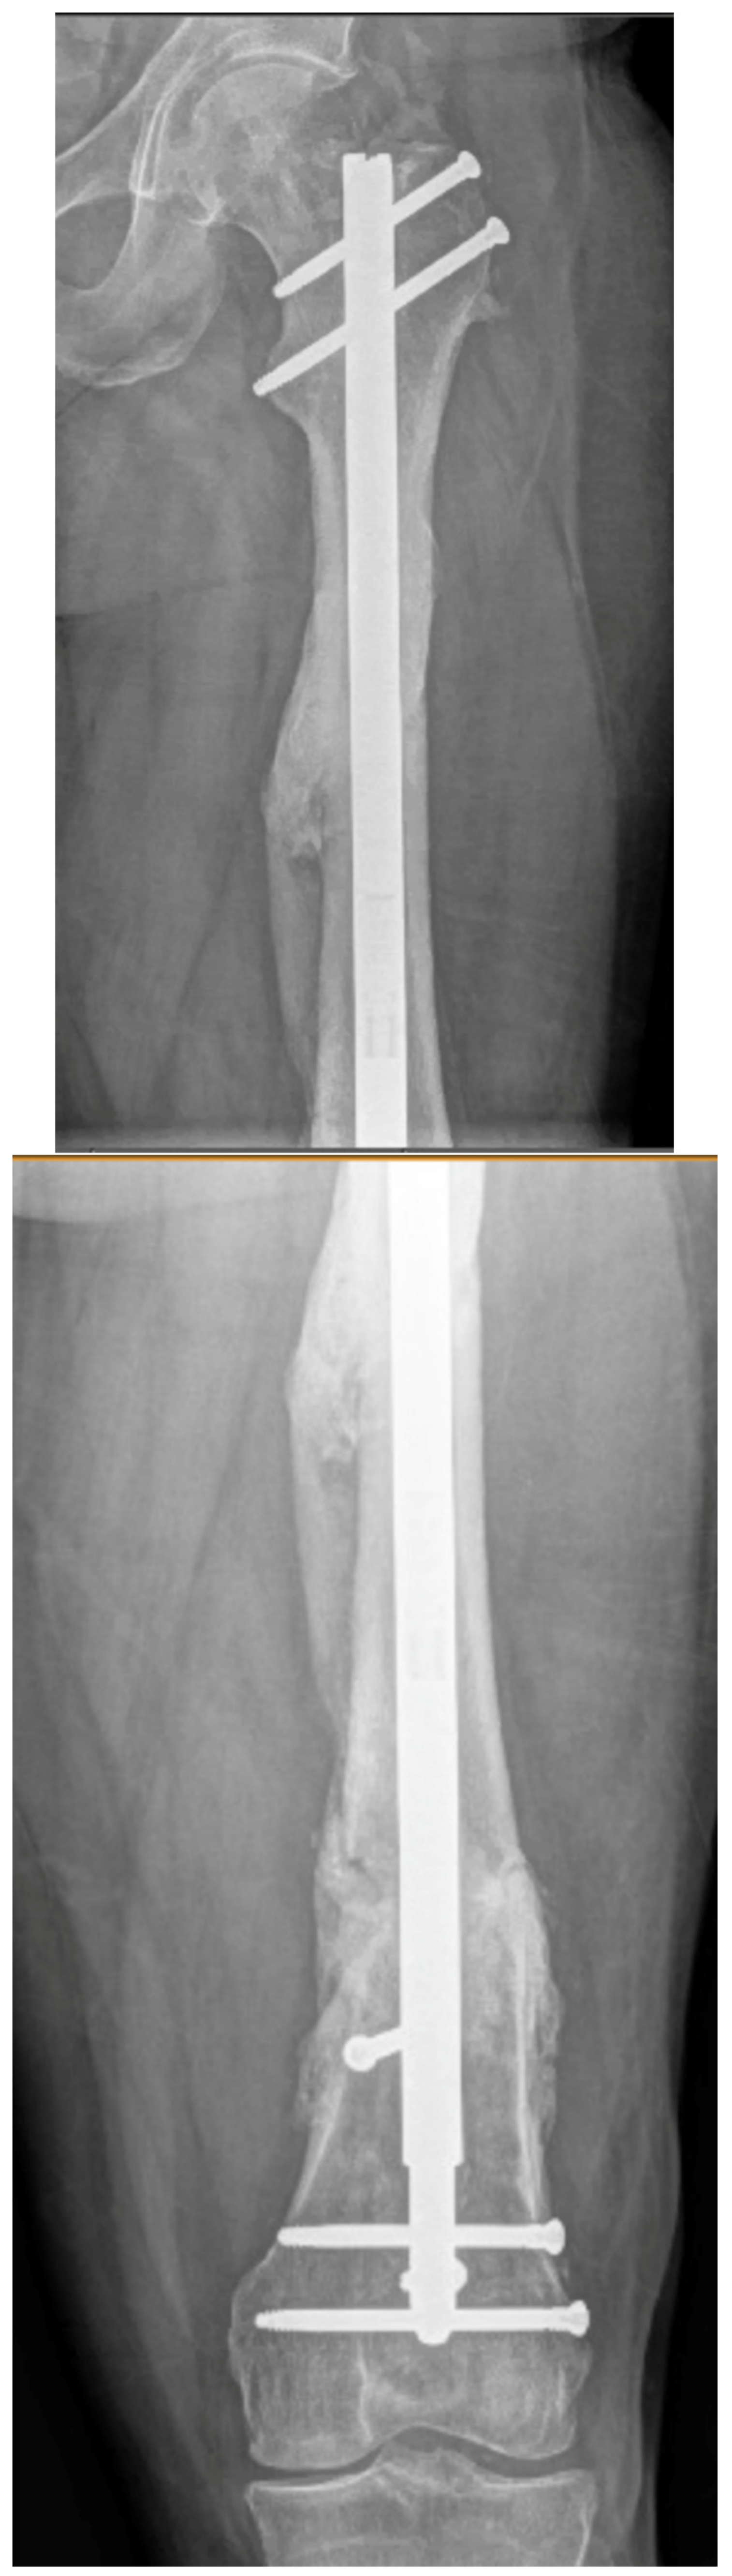

3.4. Case 4-Infected Malunion-Nonunion Femur Correction: True Dome Osteotomy

A young adult male presented new-onset diabetic ketoacidosis and sepsis. The study revealed a large thigh abscess circumferentially surrounding the left femur (Figure 9A). No other source was identified during workup. The patient underwent multiple debridements, and initially, a cortical window was made for the egress of intramedullary purulence. Subsequent debridements revealed extensive osteomyelitis. During debridement with intramedullary antibiotic nailing, the femur fractured and was eventually resected to attain source control (Figure 9B). A 13-cm segmental defect was stabilized using an antibiotic-coated locked nail with the surrounding antibiotic bone cement spacer Figure 9C). The CORA analysis revealed a five-degree varus deformity and no significant sagittal plane deformity. After source control with intravenous antibiotics and a 3-month course of oral antibiotics, the workup, including a biopsy and culture, resulted in no growth and no sign of ongoing infection. A bifocal true dome osteotomy with intercalary cortical allograft was chosen based upon a low likelihood of compliance with bone transport. A standard lateral approach elevating the vastus lateralus was used to access the femur. Reverse reamers and standard acetabular reamers were used for mating the bone surfaces (Figure 9D). The varus alignment was addressed using a blocking screw as the nail was passed; no gap was produced at the osteotomy due to its true dome shape. The dome osteotomy interfaces were autografted and compressed with a magnetic motorized nail, with additional compression at the subsequent outpatient visits (Figure 9E). The patient had soft tissue and allograft interface healing without incident and returned to gainful employment (Figure 9F).

Figure 9.

(A) A young adult male presented new-onset diabetic ketoacidosis with sepsis. He was found to have a large spontaneous left thigh abscess, as seen on CT imaging. (B) Multiple surgeries resulted in a femur fracture and subsequent segmental resection of approximately 13 cm of the patient’s femoral diaphysis. (C) The patient eventually attained source control with resection, antibiotic spacer, and an antibiotic coated nail. Patient has a 5-degree distal varus deformity. (D) The patient underwent a true dome osteotomy of the proximal and distal ends of the allograft/host bone interfaces. Fresh frozen allograft preparation using a reverse reamer is shown prior to implantation. (E) Motorized compression of the construct was employed with early and subsequent compression. Four-month follow-up showed restored neutral alignment, incorporation/interface healing of the dome osteotomy sites, bone regenerate across the interfaces, normal lab markers, and return to gainful employment. (F) Twelve-month follow-up continued to demonstrate interface healing without infection recurrence.